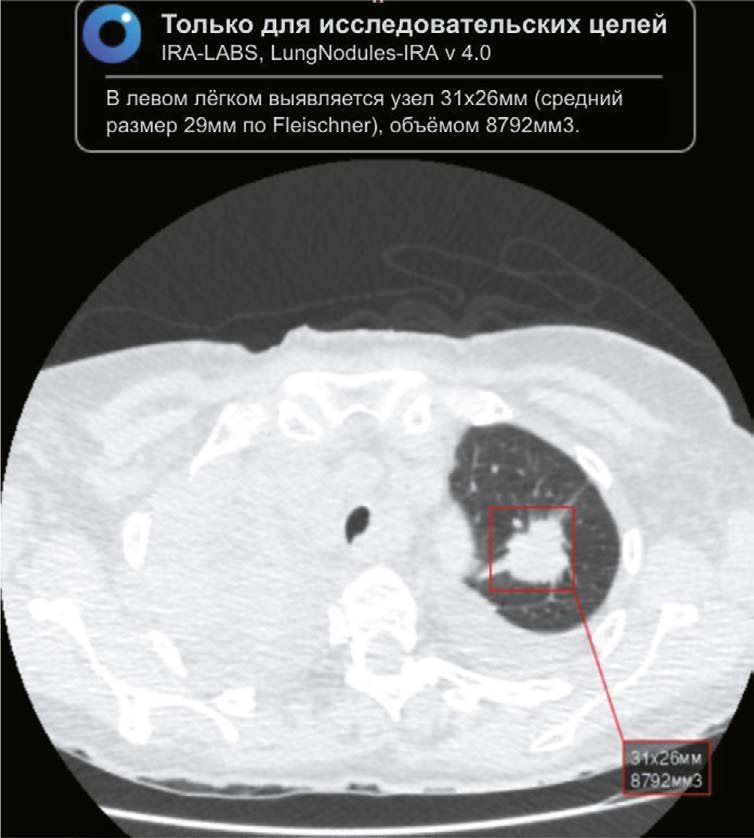

MATERIALS AND METHODS: The retrospective study included chest CT scans of patients from Krasnoyarsk krai diagnosed with COVID-19 reported in the PACS base between 1 November 2020 and 28 February 2021. The interval between chest CT and AI analysis ranged from two years and one month to two years and five months. Chest-IRA algorithm was used. AI detected lung nodules with a volume greater than 100 mm3. The radiologists divided the results into three groups based on the potential for lung cancer. The assessment of the economic benefits of using the AI algorithm considered the cost of wages and savings in the treatment of early stage lung cancer, which affects gross regional product.

RESULTS: The AI algorithm identified nodules in 484 out of 10,500 CT scans. A total of 192 patients with a high potential for lung cancer, 103 with no signs and 60 with inconclusive signs were identified, and 112 patients with a high and moderate potential for lung cancer did not seek medical care. AI confirmed 100 (28.2%) histologically proven cases of lung cancer, with stages I–II detected in 35%.